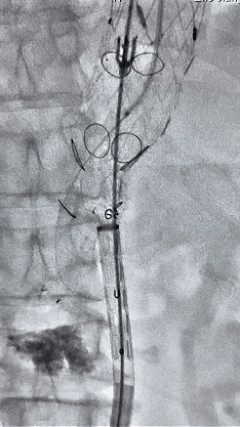

2. 左侧肱动脉入路,超选至降主动脉,更换8F-900mm长鞘,造影提示IV型胸腹主动脉瘤,累及双肾动脉。

compressed_1770972515230.gif

3. 经右股动脉导入超硬导丝,然后导入先健G-Branch 胸腹主动脉主体覆膜支架TAAA3418120e7i1010 一枚,释放主体支架至内分支打开,然后经左侧肱动脉入路,抓捕预置导丝成功后,将长鞘进入内分支出口处。

2.gif